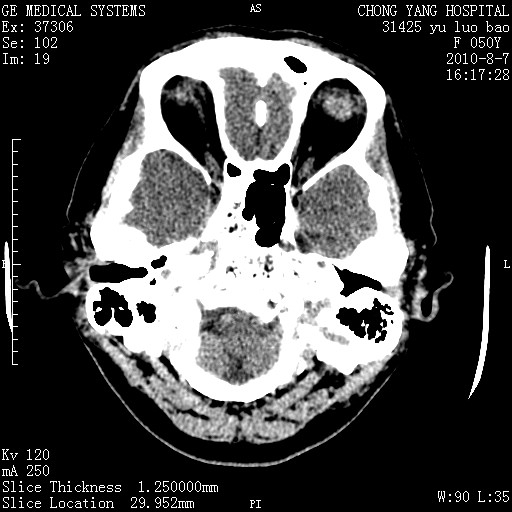

标题: CT28285:听力下降一年,头昏。 [打印本页]

标题: CT28285:听力下降一年,头昏。

右侧桥小脑角区占位--听神经瘤,建议增强或mri检查。

右侧桥小脑角去等密度占位,右侧内听道扩大、骨质吸收,考虑:右侧听神经瘤,建议增强检查。

右侧内听道扩大、骨质吸收,中脑受压左移,考虑:右侧听神经瘤,建议增强检查。支持!

右侧桥小脑角区等密度占位,内耳道扩大,听神经瘤